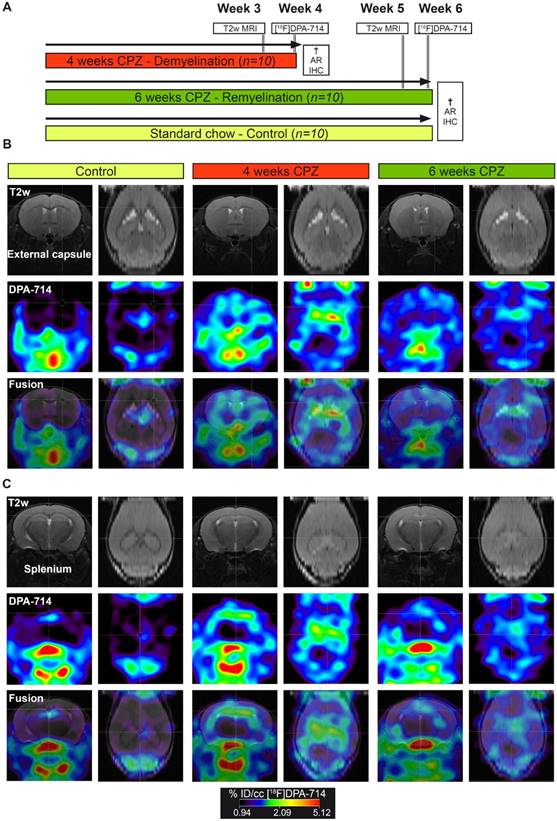

All animal experiments were performed in accordance with the German and Belgian laws for animal protection and were approved by the local bureau for animal care (LANUV, Landesamt für Natur, Umwelt und Verbraucherschutz Nordrhein-Westfalen, Germany) and the committee of Committee on Animal Care and Use at the University of Antwerp, Belgium (2016-44). Experiments have been performed and reported in compliance with the ARRIVE guidelines. n=30 female, 8 weeks old C57Bl6 (weight: 19.8 ± 1.5 g, Charles River Laboratories) were housed at constant temperature (23 °C) and relative humidity (40%), under a 12 h light/12 h dark schedule in a non-SPF environment. Food and water was available ad libitum. In order to assess microglia dynamics in vivo, mice were randomized in to a group fed with a standard rodent chow (n=10; control group) or fed with a standard rodent chow mixed with 0.2% (w/w) CPZ (Sigma-Aldrich, Germany) for 4 (n=10; demyelination) and 6 weeks (n=10; remyelination). First, CPZ-induced brain changes were assessed using T2 relaxation times MRI (Antwerp, week 3 and 5). Next, mice were transferred to Münster and the degree of neuroinflammation at de- and remyelination was assessed by [18F]DPA-714 PET (Münster, week 4 and 6) autoradiography and immunohistochemistry (Figure 1). No animal died during the experiments. All analyses and experimental procedures were performed by researchers blinded for the experimental groups.

Figure 1

In vivo PET/MR imaging of microglial activation in the cuprizone model of demyelination. (A) Experimental design. (B) Representative MR, PET and PET-MR fusion images in the external capsule region. (C) Representative MR, PET and PET-MR fusion images in the external splenium region. Abbreviations: CPZ, cuprizone; IHC, immunohistochemistry

PET experiments with [18F]DPA-714 were performed to detect temporal alterations in microglial activation during demyelination and remyelination in the CPZ model (Figure 1 A). Comparison of PET images with [18F]DPA-714 in three groups revealed increased uptake in the external capsule (Figure 1 B) and the splenium (Figure 1 C) of the CC after four weeks of CPZ treatment. Compared to week four, a decrease of [18F]DPA-714 uptake was observed after six weeks of CPZ treatment (Figure 1 B,C).